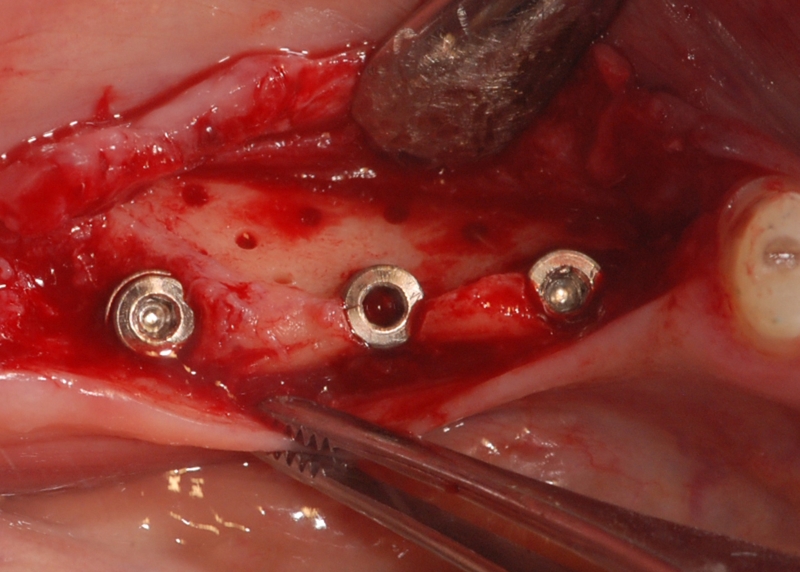

Three implants placed in a narrow posterior mandible